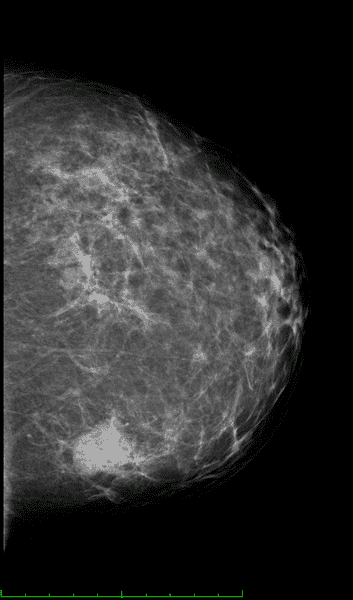

Here is a digital image of a cancer with calcifications and with a small metal marker clip (following needle biopsy). Air - black, Fat - dark gray, soft tissue - light gray, metal (including calcium) white.

Hi TCups, Regarding the xray you attached what is it that looks like cob webs? What makes that pattern?

It's a bit of an optical illusion... sort of.

You're looking at a breast which has thickness, but compressed into 2D. There are regions where there's a greater density of connective tissue, fats, muscles etc. Where those regions overlap, one, two, or more times you have less exposure, right? What about when there's relatively low density?

So, it's just the same patterns you'd see in any fleshy mass if you took the entire volume and x-rayed it. The art of reading films is that you learn to recognize which tissues create what kind of shadows, and so much more.